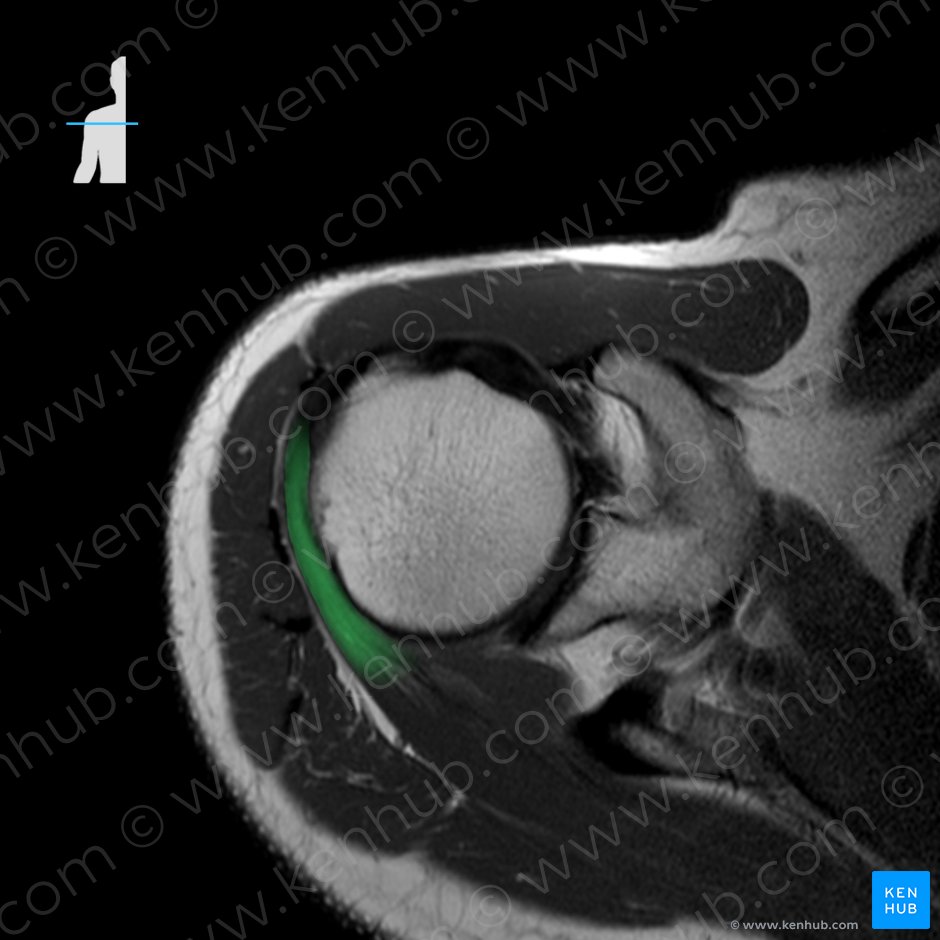

2. 견갑하근(Subscpularis, 어깨밑근)

origin : 견갑골 전면의 견갑하와

(Subscapular fossa of scapula)

insertion : 상완골 소결절

(Lesser tubercle of humerus)

function : Shoulder joint: Arm internal rotation

Stabilizes humeral head in glenoid cavity

견갑하근은 어깨의 내회전, 내전에 관여하며

4개의 회전근개 중 가장 크고 두꺼우며 강한힘을 내는 근육입니다.

견갑골의 앞쪽에 위치하여, 침습적 접근이 어려운 부위로

마사지나 테이핑 등을 통해 접근합니다.

견갑하근의 경우 어깨 후면에서 팔, 주관절 부위로 방사통이 나타납니다.

손목에 띠 같은 부위로 방사통이 나타나는 것이 특징인데,

대부분 손등이 손바닥보다 압통과 통증시 심합니다.극하근과의 차이점은,

엄지손가락을 위로한 상태로 외전시 통증이 심화됩니다.